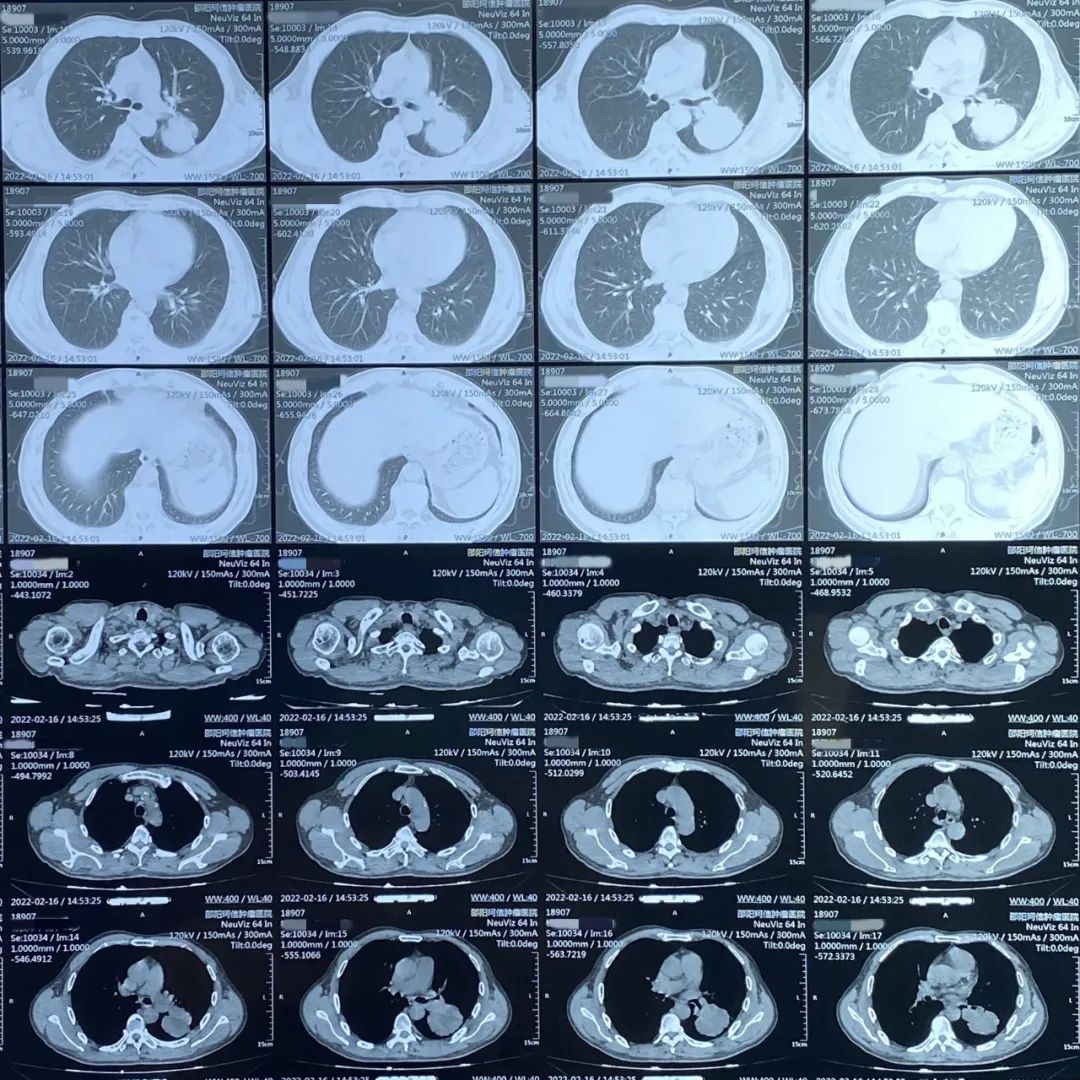

患者:男性,61歲,肺部腫瘤

患者因經(jīng)常出現(xiàn)咳嗽、胸悶、氣喘等癥狀入院檢查,經(jīng)CT檢查所示左肺有占位,病理活檢確診為肺部腫瘤。

肺部CT診斷